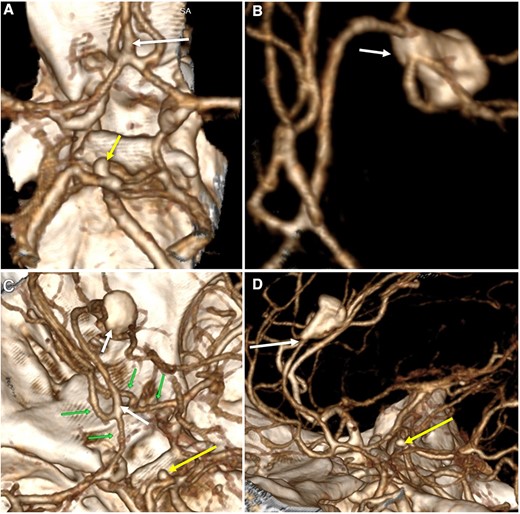

A multislice computed tomography (CT) without contrast revealed an extensive interhemispheric hematoma in the frontoparietal region, subarachnoid hemorrhage, and intraventricular hemorrhage in the adjacent area (Fisher grading score of IV) (Fig. 1). In addition, cerebral angiotomography and 3D reconstruction imaging suggested the presence of two abnormal vascular lesions: (i) a fusiform aneurysm of 12 × 7 mm in an accessory A2 portion of the ACA and (ii) an unruptured saccular aneurysm of 3.3 × 2.8 mm in the distal segment of the basilar artery adjacent to the anterolateral surface of the P1 segment and the left superior cerebellar artery (Figs 2 and 3).

Three-dimensional reconstruction imaging. (A) Superior view of the Circle of Willis shows a variant of the ACA with an accessory A2 branch (white arrow) and a saccular aneurysm of 3.3 × 2.8 mm at the basilar artery (yellow arrow). (B) Inferior–superior view depicts the configuration of the ACA with a triplicated A2 segment and a fusiform aneurysm of 12 × 7 mm emerging in its distal portion, with branches arising from the aneurysm sac (white arrow). (C) Superior view of the anterior and posterior circulation exhibits the complex anatomy of the A1 and A2 segments (green arrows), the accessory A2 segment and distal fusiform aneurysm (white arrows), and the basilar aneurysm (yellow arrow). (D) Lateral view shows the course of the triplicated A2 segment with the fusiform aneurysm arising distally (white arrow) and the small basilar aneurysm (yellow arrow).